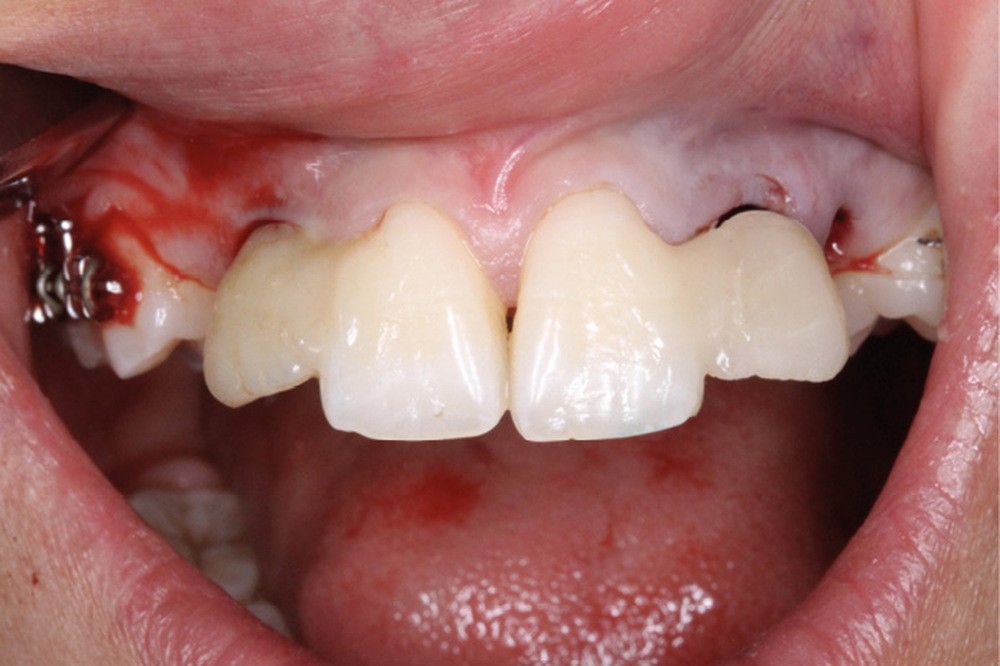

Les extractions de 12, 22, 63, 34 et 44 ont été réalisées dans un premier temps. Un cache esthétique en résine composite a été élaboré à partir d’une clé en silicone obtenue sur les empreintes initiales et collé sur 11 et 21 afin de limiter l’impact psychologique de telles extractions (fig. 2a-b).

La désinclusion des canines a été réalisée dans un deuxième temps opératoire après trois semaines de cicatrisation muqueuse afin d’avoir une quantité de gencive attachée suffisante lors de la réalisation des lambeaux. Un lambeau déplacé apicalement a été réalisé pour désinclure la 13, avec une direction de traction distale sur une potence soudée sur le sectionnel activée après trois semaines de cicatrisation (fig. 3). Un lambeau muco-périosté repositionné a été réalisé pour désinclure la 23 qui a été immédiatement mise en charge par traction distale sur un bouton palatin collé sur 25. Un approfondissement vestibulaire mandibulaire antérieur a ensuite été réalisé.